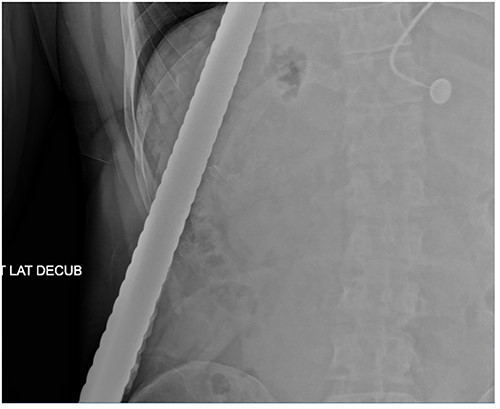

A 43-year-old male patient presented to the emergency department after falling onto an exposed rebar at work at a construction site. The rebar entered the patient’s left flank and exited via the anterior aspect of the left chest. His initial blood pressure was 137/96 and his heart rate was 114 beats per minute. Physical examination revealed a rebar measuring ~80 cm impaled through the patient’s left flank and left chest (Fig. 1). While in the trauma bay, an abdominal X-ray was obtained, demonstrating a right-sided pneumothorax, and the rebar’s path was extending into the left anterior thoracic cavity (Fig. 2). Afterward, the patient was taken to the operating room where a left thoracotomy and exploratory laparotomy were performed.

Abdominal X-ray demonstrating the rebar trajectory into the left anterior chest; the path is distorted secondary to patient positioning during imaging.